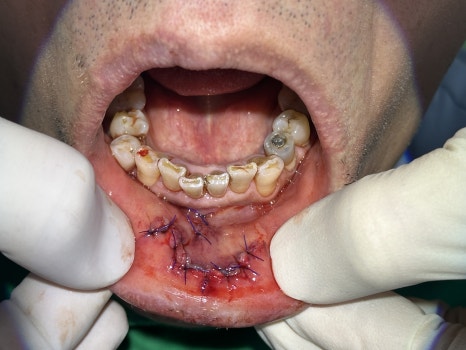

📌 사고 직후, 응급실 같은 현장

환자분은 119 구급대에 의해 저희 병원으로 바로 안내되었습니다.

넘어지며 입술이 깊게 찢어지고, 앞니가 부러져 흔들리는 외상을 입으신 상황이었습니다.

입술 외측 6cm, 내측 4cm 관통 파열

윗 앞니 다수 탈구 및 흔들림

즉시 치아 재위치 후, 레진-와이어 스플린트로 고정

🖼️ 입술 외상 사진 / 앞니 파절 및 고정 사진 / X-ray 사진

외상 직후 찢어진 입술 / 앞니 탈구 고정한 초기 응급처치 사진